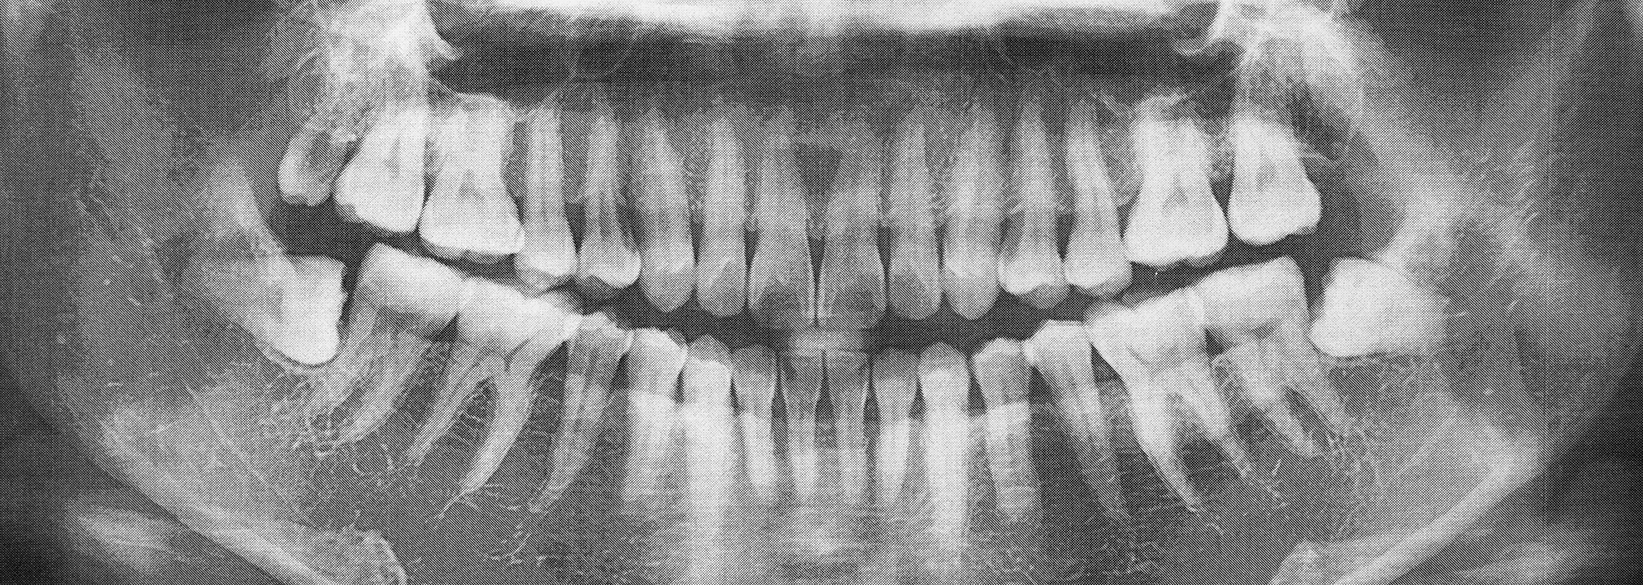

As diets and facial structures have evolved over time, wisdom teeth have posed more oral health risks than benefits. Fortunately, our dentists at Kovar Dental can remove them so that additional space is provided and concerns about infection and dental pain are no more. If you or your teenager need help saying goodbye to your wisdom teeth, call our office to schedule an appointment to ask about wisdom tooth extractions in Fredericksburg.

The process of removing wisdom teeth can be fairly straightforward. We’ll either perform a simple or surgical procedure. If the teeth are visible above the gumline (partially erupted), we can use special instruments to gently loosen them until they detach from the connective tissues. If the molars are beneath the gumline (impacted), a surgical approach must be taken. A small incision is created in the gums so that each tooth can be removed swiftly and successfully.